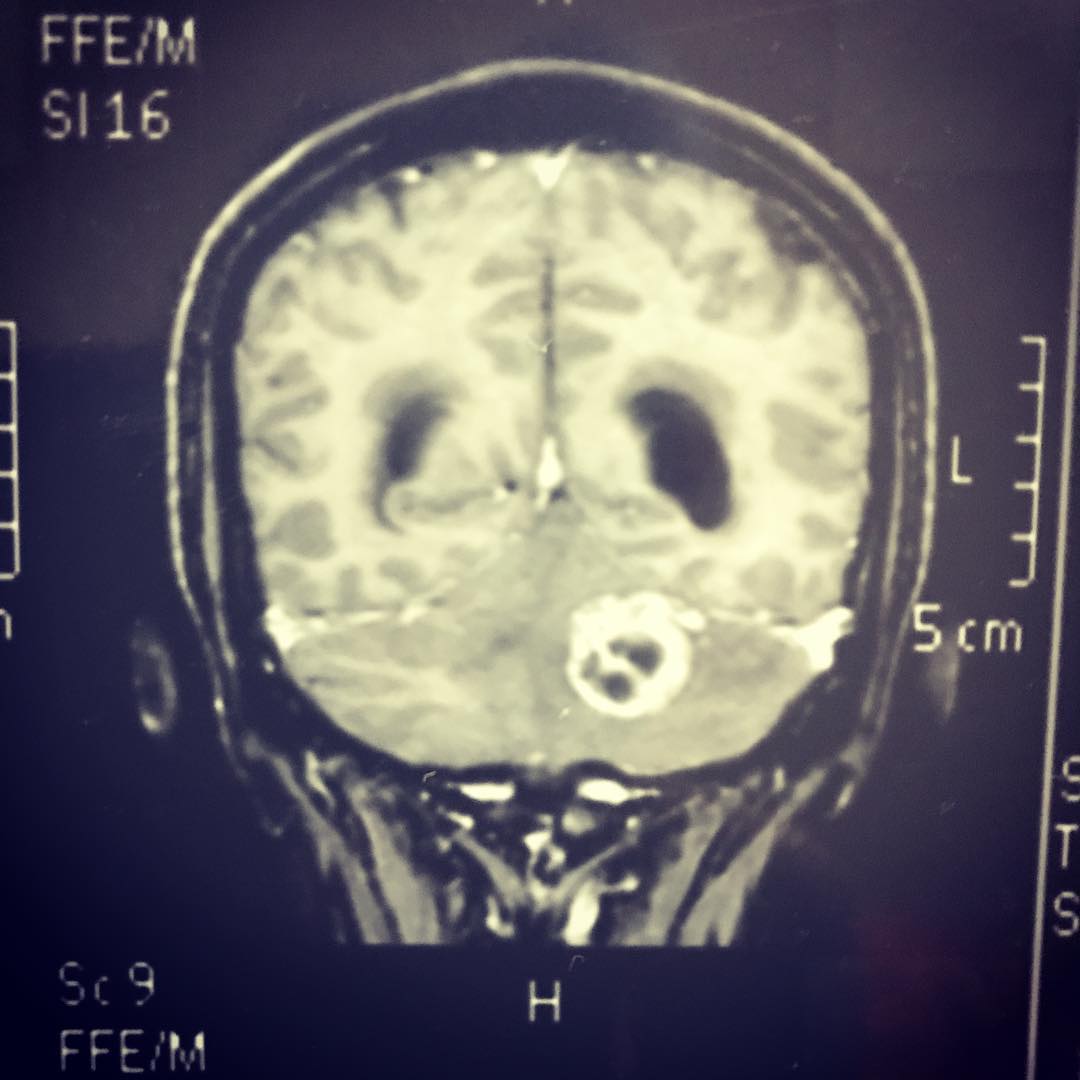

Cirugía tumores cerebrales

Cirugía para hidrocefalia